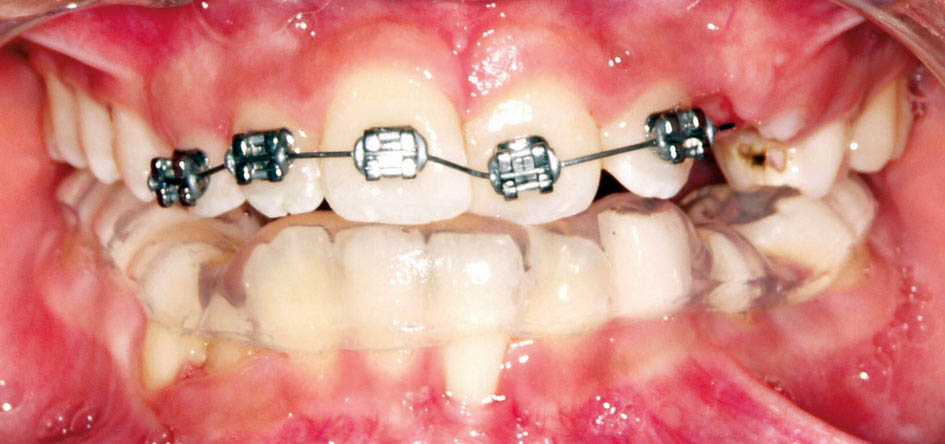

استفاده از RPE و پروترود شدن قدامیهای بالا با هم انجام میشود (شکل 42-5) و کلاً کمتر از 6 ماه طول میکشد. در دومین هفته درمان RPE، انحراف مندیبل اصلاح میشود و چانه به وسط صورت میآید. میدلاین دندانها هم به دنبال آن اصلاح میشود (شکل 42-5). البته اصلاح انحراف مندیبل در سنین کم مقدور است و در سنین بالا بسیار سخت درمان میشود.

شکل 42-5: کراس بایت خلفی و قدامی با هم درمان گردیده است.